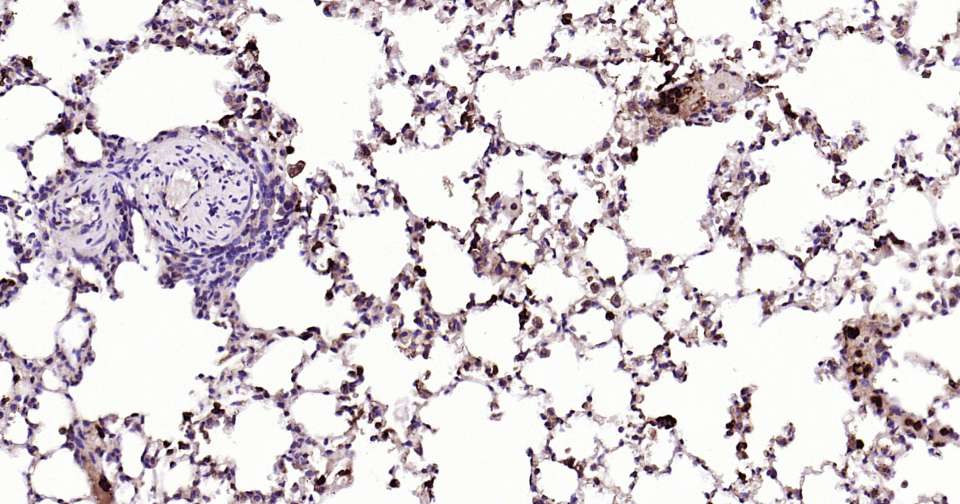

Immunohistochemical analysis of paraffin embedded mouse lung tissue slide using IHC0335M (Mouse S100A8 Kit).